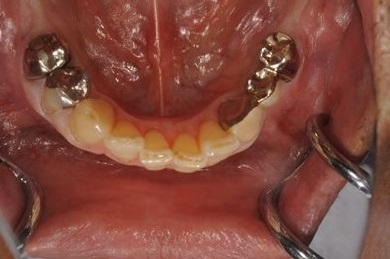

インプラントの症例写真 IMPLANT

| 性別/年齢 | 男性 / 61歳 | ||||||||||||||||||||||||||||||||

| 主訴 | 奥歯のインプラント治療を希望。 | ||||||||||||||||||||||||||||||||

| 治療内容 | インプラント4本、メタルボンドセラミッククラウン4本 | ||||||||||||||||||||||||||||||||